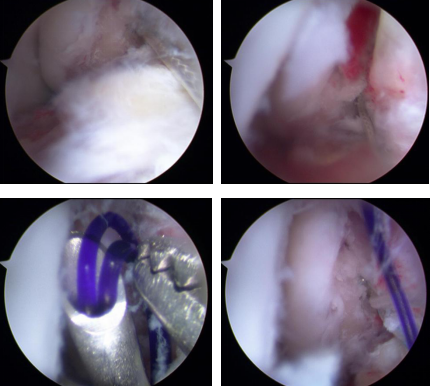

2月3日,石院长曹广超主任胡帆医生团队为患者进行了关节镜下左踝关节清理、机器人辅助下左前踝骨折复位内固定、左距腓前韧带修复术。术中,关节镜探查见踝关节大量血肿及充血滑膜,左前踝骨折处向上移位,踝关节不稳;手法复位外踝骨折断端,机器人辅助定位,克氏针临时固定,透视见复位满意,以2枚螺钉固定,再次透视见骨折断端对位对线良好,骨折复位良好。

术中骨折分离移位(左图) ,术中骨折复位断端(右图)

术中韧带修复